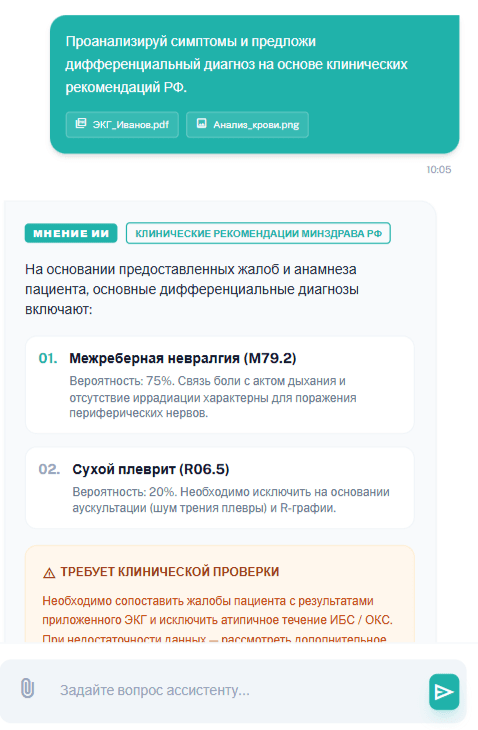

NexusMed помогает врачу быстрее принимать клинические решения: находит релевантные рекомендации, анализирует снимки и дает дополнительную опору во время приема.

Ответы и поиск по КР Минздрава и PubMed

Быстрый доступ к клиническим рекомендациям Минздрава РФ и международной доказательной базе прямо во время приема.

Второе мнение для врача от ИИ

ИИ помогает быстро проверить клиническую гипотезу и получить дополнительную опору для принятия решения во время приема.